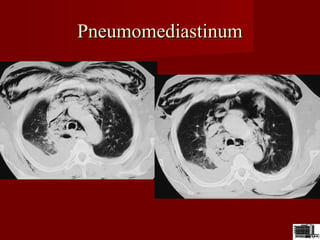

PneumomediastinumPneumomediastinum

Paramediastinal

sting opacitate

liniara subtire care

inconjura butonul

aortic de care este

separat printr-o

hipertransparenta de

1-3mm